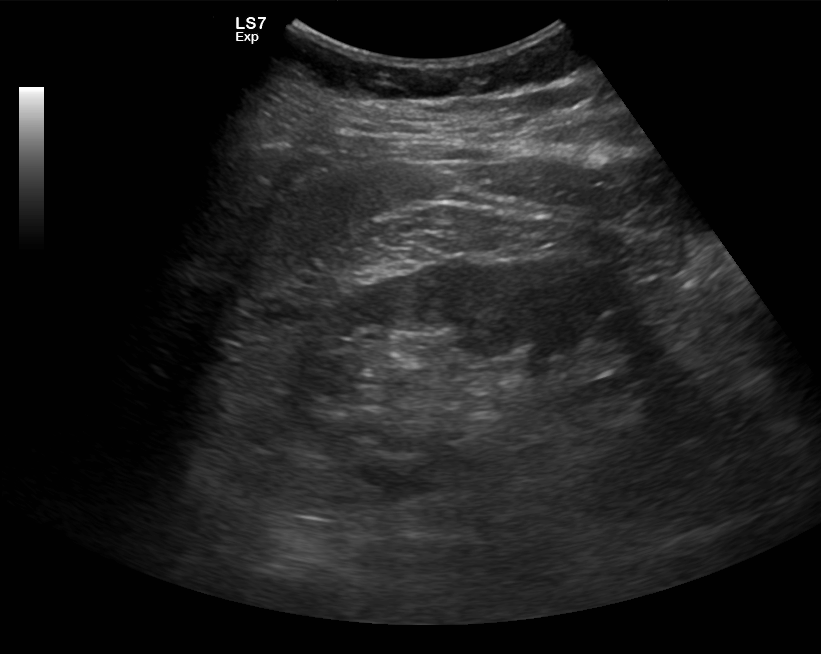

Virtsaelinten, eli munuaisten, virtsarakon ja eturauhasen ultraäänitutkimus

Virtsaelinten ultraäänellä arvioidaan esimerkiksi tihentynyttä virtsaamistarvetta, virtsaamisvaikeuksia tai virtsan verisyyttä. Tutkimuksessa kuvataan yleensä munuaiset ja virtsarakko sekä miehillä lisäksi eturauhanen.

Mitä virtsaelinten ultraäänitutkimuksella voidaan todeta

- Munuaisten hyvän- ja pahanlaatuisia kasvaimia

- Virtsankulun estyminen (hydronefroosi)

- Miehillä eturauhasen suurentuminen

- Virtsarakon seinämän kasvaimia